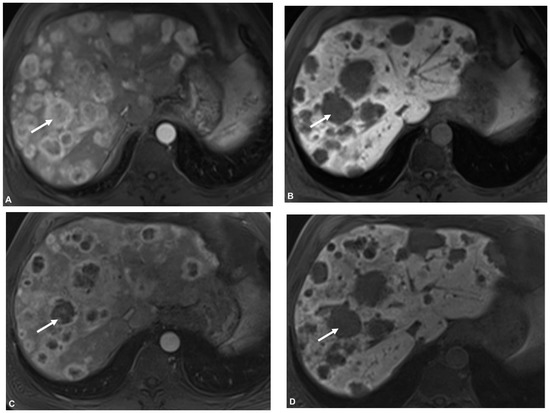

2.3. MR Imaging

2.4. PET/CT

2.5. Image Analysis